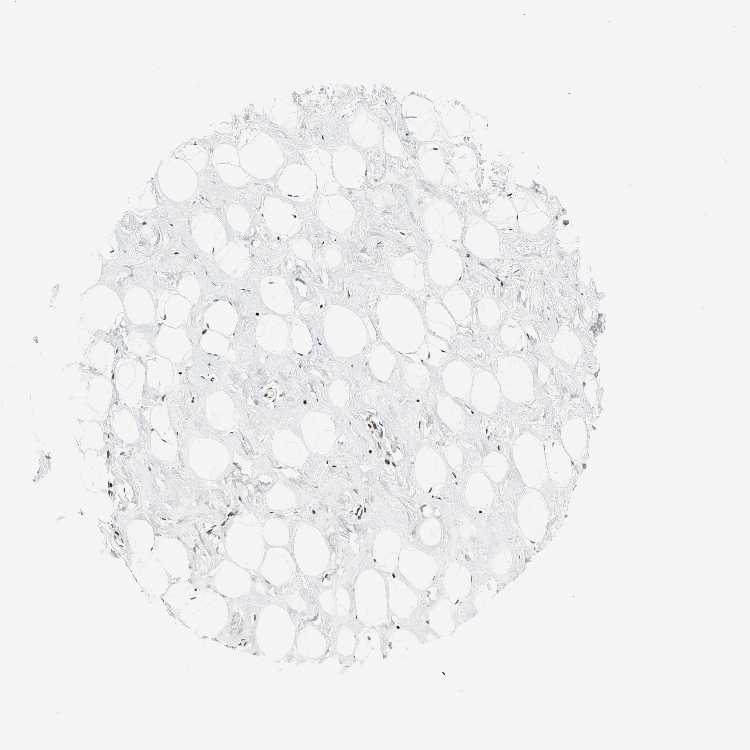

Antibody CAB004208

Adipocytes High

Glandular cells High

Myoepithelial cells Medium